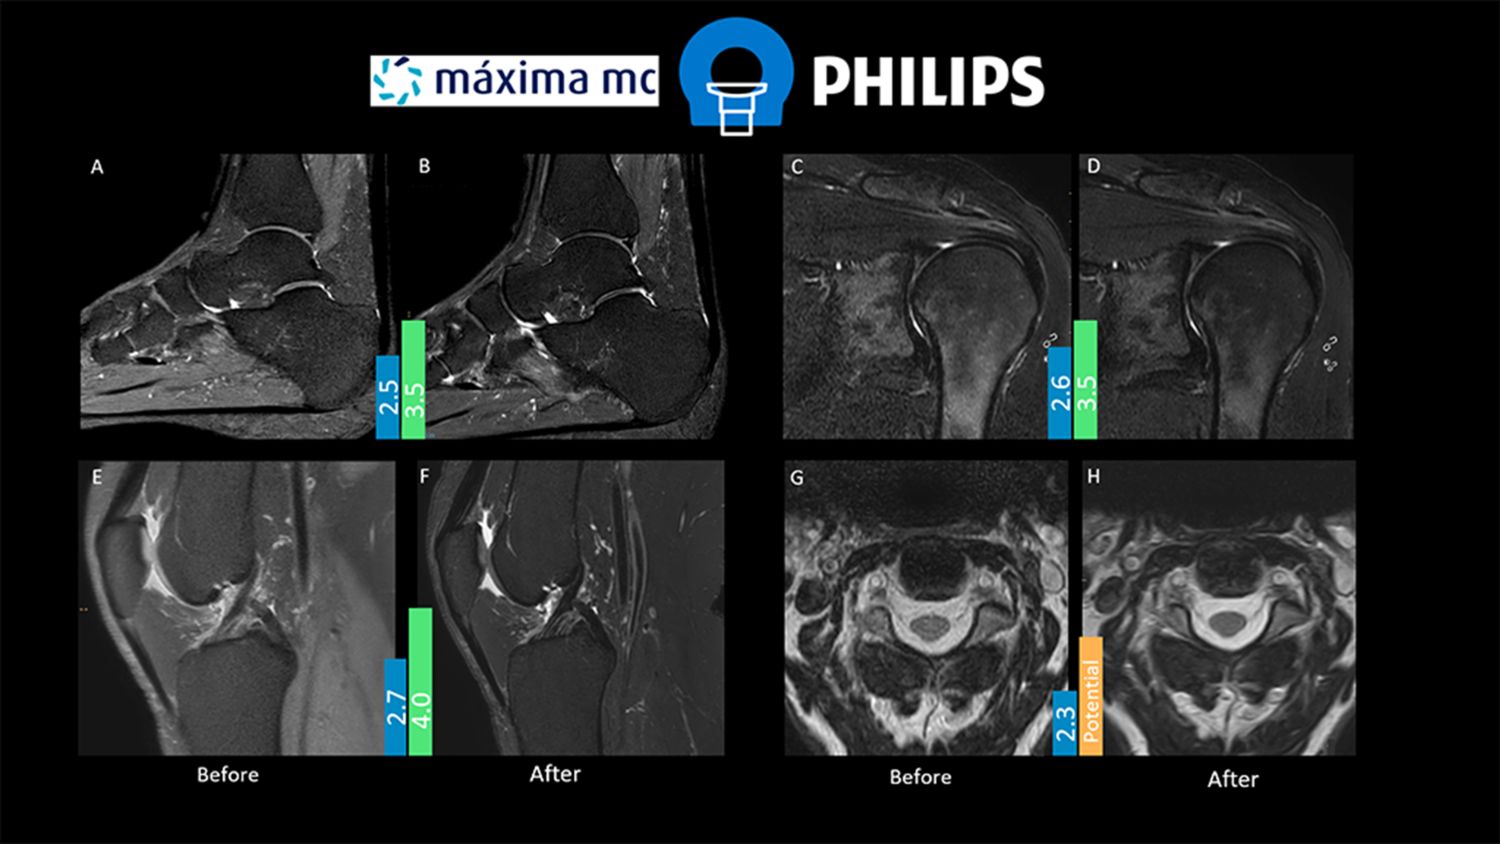

To evaluate the optimized protocols, a 5-point scale was created to assess signal-to-noise, contrast-to-noise, sharpness/resolution, and artifact level. The radiologist reviewed several patient cases before and after optimization and scored the image quality. The average scores are displayed in figure 1.

Figure 1. Images displayed comparing before [A, C, E, G] and after protocol optimization [B, D, F, H]. Scores in blue bar indicate average result before the optimization. Scores in green bar indicate the average IQ result after protocol optimization.